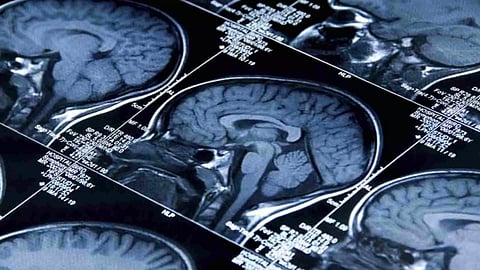

The researchers used machine learning (ML) -- a type of AI that help machines learn and improve from data analysis without explicit programming -- looked at cortical thickness and surface area, along with volumes of deep-lying brain regions.

However, it is unclear which brain processes are involved in these anxiety disorders, the researchers said.